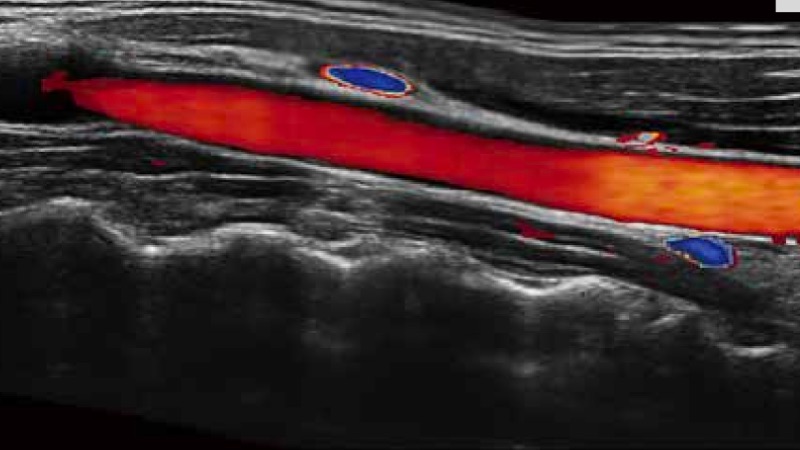

SR Flow高分辨率血流成像

高分辨率血流成像技术提高了对低速血流信号的检测能力。在提高空间分辨率的同时,也克服了血流外溢现象,为用户提供更加真实的血流动力学信息。

通过彩色血流和实时宽景相结合,可观察到完整的动静脉血流,方便医生检查。实时扫查过程中,如有任何操作失误也可以很容易地进行回扫擦除,而不会中断扫查。